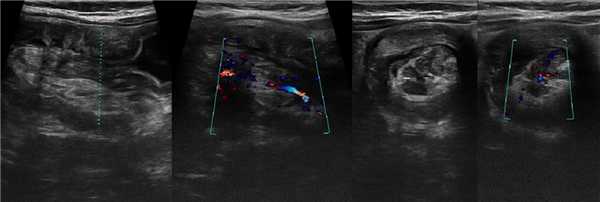

Рисунок. Женщина 55-ти лет на протяжении 2-х недель жалуется на боль в животе. На УЗИ внизу живота слева определяется слоистая структура протяженностью 3 см (1), на поперечных срезах похожа на «мишень» (2) и «бублик» (3, 4). Заключение: Эхо-признаки инвагинации кишечника. Через 6 часов на КТ петли тонкой кишки несколько отёчны, другой патологии не выявлено. Обратите внимание, короткие кишечные инвагинаты могут расправляться самопроизвольно, поэтому пациента следует наблюдать некоторое время.

Рисунок. Девочка в возрасте 10-ти месяцев поступила в больницу с резкой приступообразной болью в животе, кал с кровью. На УЗИ в брюшной полости определяется цилиндрическая масса с гиперэхогенным центром и гипоэхогенной периферией — «псевдопочка». На поперечных срезах образование походит на «бублик»; можно рассмотреть гипоэхогенные внешний и внутренний цилиндр тела инвагината, а так же гиперэхогенный жир брыжейки с округлыми лимфоузлами. При ЦДК в сосудах брыжейки определяется кровоток. Заключение: Эхо-признаки инвагинации кишечника.